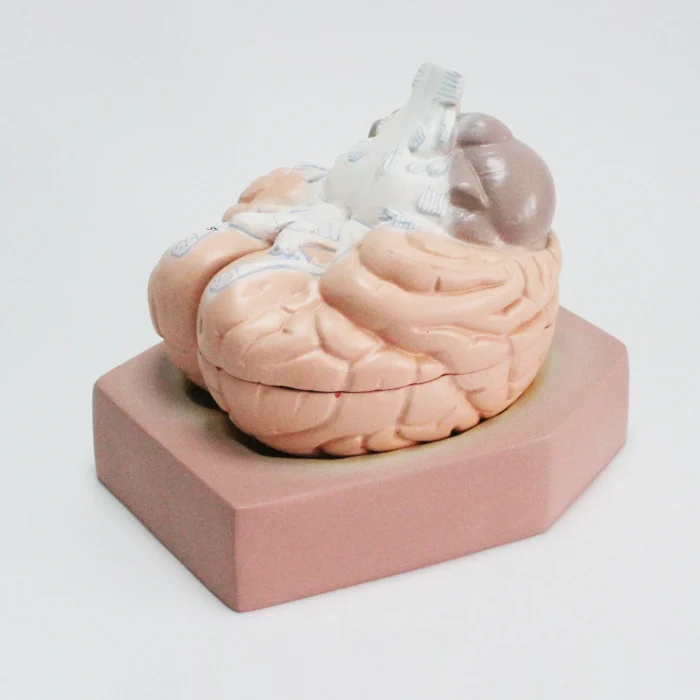

Modèle anatomique de cerveau humain

TND 199,000 Le prix initial était : TND 199,000.TND 168,000Le prix actuel est : TND 168,000. TTC

Modèle de cerveau humain

4 parties : (Fabriqué à partir de fibre de verre)

Modèle anatomique de cerveau humain

4 parties : (Fabriqué à partir de fibre de verre)

Ce cerveau est médialement divisé en deux parties, la moitié droite peut être démontée en frontal avec les lobes parentaux, le tronc cérébral avec les lobes temporaux et occipitaux en deux parties. Placé sur une base amovible avec Key Card numérotée.